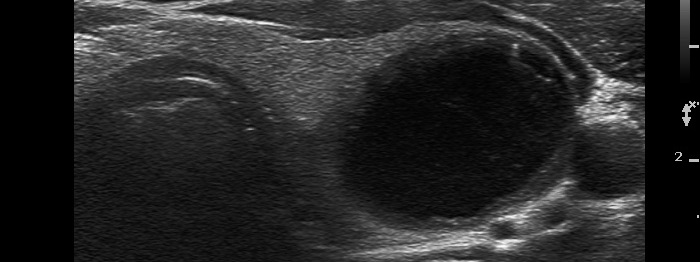

Follicular adenoma (histological diagnosis)

Before aspiration of 2 mL cystic fluid |

There are numerous hyperechogenic granules in the lower pole of the nodule. These figures might be confused with punctate echogenic foci (microcalcifications), as happened in this case. However, several have dorsal tail and therefore the remaining without a tail likely belong also to the same subgroup.